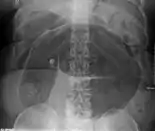

- Abdominal x-ray – tire-like shadow arising from right iliac fossa and passing to left

Coffee bean sign in a person with sigmoid volvulus

An x-ray of a person with a small bowel volvulus.

Plain X ray of a cecal volvulus